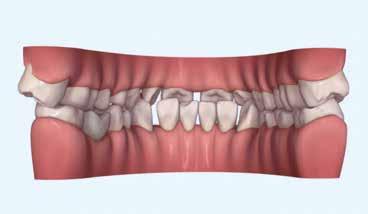

Hölgy páciensem az első konzultáció során tipikus kórtörténetet vázolt fel: Gyermekkora óta szeretett volna fogszabályozó készüléket, hiszen mindig is zavarta a class 2-es eltérésnél tipikusan jellemző nagy overjet (1-3. képek), és természetesen az ezáltal kifelé álló felső metszőfogai, részben a felső metszők protrúziója, részben pedig a disztálisan elhelyezkedő mandibula miatt. Annak ellenére, hogy több fogszabályozó szakorvosnál is járt az évek során, de mivel saggitális eltérése és az alsó metszőfogak torlódása miatt négy kisőrlőfog extrakcióját, illetve emellett sokszor állcsont műtétet is javasoltak neki, nem vágott bele a kezelésbe (4-5. képek).

A konzultáció során arról is beszéltünk – ahogy az ilyenkor lenni szokott –, sohasem szeretett igazán mosolyogni, de a Pitts Protokolloknak köszönhetően az arc- és mosolyesztétikai céloknak megfelelően kerül megvalósításra az okklúziós korrekció. Az okklúziós kezelési célok az alábbiak voltak: a felső és alsó fogív nivellálása és tágítása, az alsó fogsor/ mandibula mezializálása, valamint a harapás megemelése által a mélyharapás rendezése.

Az esztétikai kezelési céloknál a Pitts elvek szerint a legfontosabb fogak a felső, középső metszők, a cél ezeknek a tökéletes pozícióba állítása. A legfontosabb, hogy a felső, középső metszők labiális felszíne merőleges legyen a Frankfurti Horizontálisra, vagyis természetes fejtartásnál (Natural Head Position) párhuzamos legyen a vertikális síkkal (6. kép) Ehhez az ideális pozícióhoz képest minél protrudáltabbak a felső metszők, annál laposabb, szemből nézve kevésbé ívesebb lesz a mosolyvonal, másrészt optikailag a metszők

hossza is rövidül, azaz a Vertical Incisor Display (Metszőfog láthatóság) csökken. A miniesztétikai, vagyis a mosolyesztétikai eredmény szempontjából egyik jelenség sem kívánatos. A mikroesztétika (a fog- és ínyesztétika) is szorosan hozzátartozik az esztétikai paraméterekhez, ennek tökéletesítése is minden esetben a célok közé tartozik fogkontúrálással vagy esztétikai fogászati felépítéssel, továbbá interproximális redukcióval és szükség esetén lézeres ínykontúrálással (7. kép).

A kezelést Pitts-21-es fogszabályozó készülék alkalmazásával végeztük el. A felső fogíven mosolyvonal beállító esztétikai (Smile Arc Protection - SAP), az alsó fogíven a Spee görbe kiegyenlítését szolgáló funkcionális bracket pozicionálást

alkalmaztunk. Előbbi elengedhetetlen a szép, íves mosolyvonal kialakításához, utóbbi pedig az alsó fogsor mezializálásához, és így az első osztályú sagittális okklúzió kialakításához. Az alsó metszők torlódásának feloldására tolórugókat alkalmaztunk az első hónapban (8. kép)

A protokollok szerves része a mesterséges harapásemelés, melynek segítségével – mintegy kivéve a rágóerők fogmozgatásokat akadályozó hatását – segítjük fogszabályozó rendszer működését. Ezek a ragasztásnál az alsó 7-esekre, majd később a felső 4-esekre kerültek (9. kép).

A harapást beállító elasztikus gumihúzásokat, mint minden kezelésnél, ebben az esetben is folyamatosan, az egész ke-

zelés alatt 24 órában (étkezések kivételével) viselte a páciens. Segítségükkel történt az alsó fogsor mezializálása, és a harapásemelésben is fontos a szerepük a disztálharapás korrekciója során. Az utolsó hónapokban az okklúziós finomítások is részben a segítségükkel történnek az ívhajlítások mellett (10. kép).

A fogkontúrálás és az interproximális redukció alkalmazásával a mikroesztétikai részletek tökéletesítése is megtörtént (11. kép) A kezelés mindössze 16 hónapig tartott, megtörtént a rágófunkció helyreállítása, és az esztétikai végeredmény sokéves várakozás után valóban fordulópontot jelentett páciensünk életében (12-14. képek).